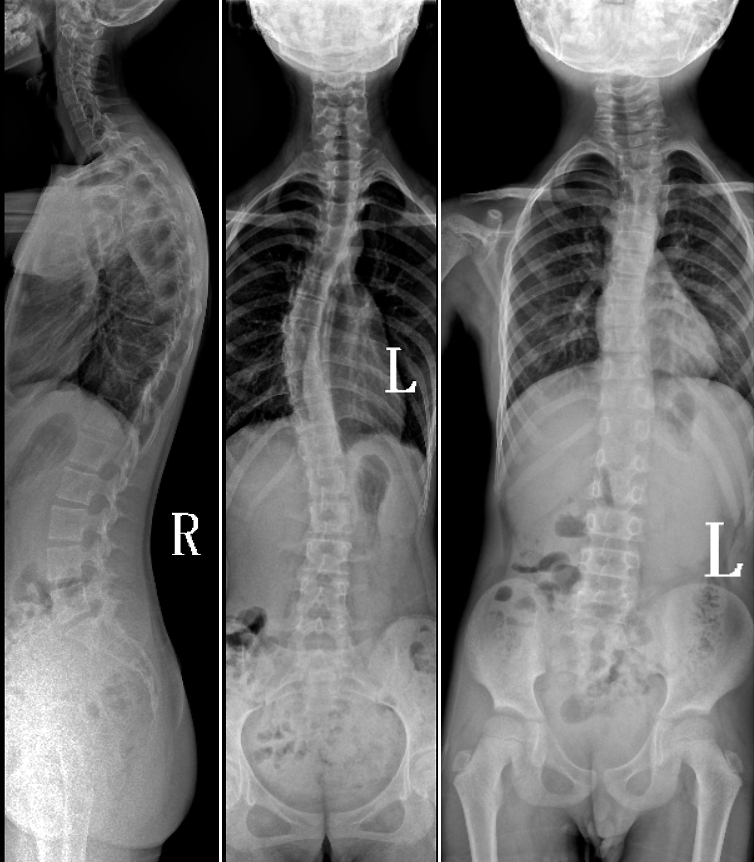

DR是臨床骨科的重要檢查手段之一。在骨科檢查中,脊柱矯形、長骨骨折、腰椎退行性病變等,需要采集脊柱、下肢全景圖像,輔助醫(yī)生臨床診斷,從而制定科學(xué)的治療方案,普愛醫(yī)療的大視野平板動態(tài)DR就像是一座橋梁,連接起現(xiàn)代醫(yī)療技術(shù)與當(dāng)?shù)厝嗣竦尼t(yī)療需求。

普愛醫(yī)療自主研發(fā)的大視野平板動態(tài),采用17"*34"的有效視野,一次曝光即可得到全脊柱或全下肢影像。相較于多張攝影再軟件拼接的DR設(shè)備,PLX8600解決了拼接圖像存在密度不均勻,拼接處圖像配準(zhǔn)和放大效應(yīng)等問題,給臨床帶來了真正的大視野影像解決方案。

除了常規(guī)靜態(tài)攝影外,PLX8600的大平板具備動態(tài)透視和點片功能,能夠很好地觀察復(fù)雜部位病灶,有效地抓取關(guān)鍵幀,降低患者多次攝片的概率。如:全脊柱狀態(tài)評估、長骨關(guān)節(jié)活動度、下肢靜脈造影瓣膜功能評估、消化道功能評估、脊髓造影等更多大視野臨床應(yīng)用,“多面手”都能輕松應(yīng)對。